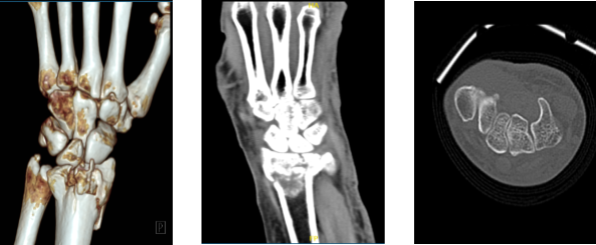

The patient presented today is 68-year-old, female and having a complaint of her left hand and wrist after getting injured because of a fall. Her Xray result showed a fracture but we wanted to make sure of the diagnosis. We agreed to take CT-Scan.